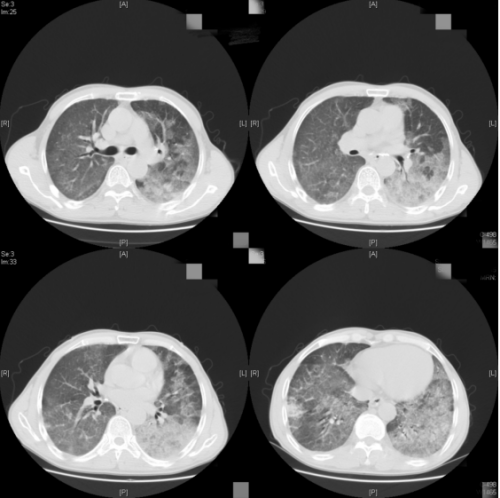

“目前主要治疗方案为全肺灌洗和粒细胞-巨噬细胞集落刺激因子治疗。其中大容量肺泡灌洗术是一种确切有效的治疗手段,而此类手术需要强大的麻醉支持,具有一定的风险,需要医疗团队密切协作才能完成。”科主任杨红忠、副主任刘胜岗和副主任医师刘超群等组成的专家团队充分讨论后,决定为他进行大容量肺泡灌洗术,在全麻支持下双腔气管插管单肺通气下,前后进行了左肺及右肺两次大容量肺泡灌洗。每次历时5小时,每侧灌洗恒温生理盐水15000ml,回收14800ml,回收率达98.7%。手术很顺利,常先生被转回普通病房,科室对他的灌洗液再次进行病理送检,证实为肺泡蛋白沉积症。术后,他呼吸困难症状明显改善,活动耐量大幅提升。

灌洗之后复查CT影像,较之前明显吸收